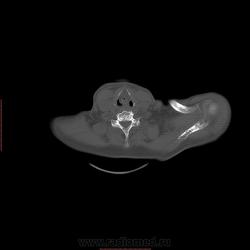

Пациент 1946 г.р., состоит на Д учете в онкодиспансере по поводу с-ч кожи (базалиома), прошел курс лучевой терапии, в 2009г на Ргенографии выявили образование 7 ребра, направили на Кт, на КТ (2009г) был выставлен д-з ГКО, пункционная биопсия не произведена. А сейчас вот такая картина, с множественными литическими очагами в костях грудного склета + образование 7 ребра, с отрицательной динамикой.

повторно взяли пациента, сняли кости таза, такая же картина- множественные очаги литической деструкции. Заключение: больше данных за миеломную болезнь.